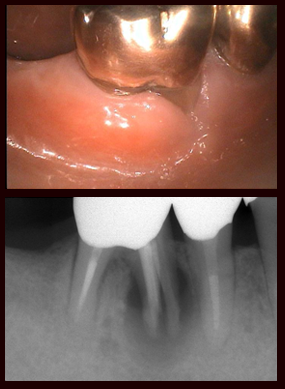

治療前

この患者さんは右下の第一大臼歯の痛みで来院されました。レントゲンで近心根が破折しているのがわかります。

抜歯した歯

まずこの歯を抜歯し、きれいに処置して破折部分を特別なセメントで接着します。接着面の処置を行い、再び抜歯窩に戻し固定します。